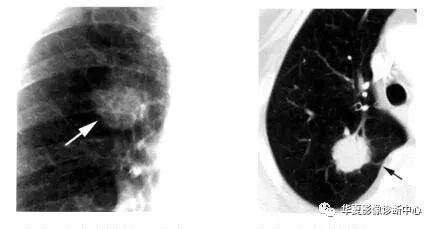

(4)医生,结节中出现了黑黑的小孔洞是什么?

那就是支气管,因为支气管有空气,空气在CT中是纯黑色的,它有个形象的专业名称叫做支气管充气征。充气支气管通常见于肿瘤性肺结节中(25% - 65%的病例),这是腺癌或细支气管肺泡癌最典型的征象,但充气支气管在良性病变中很少见。

(5)医生,如果结节中间是个大空洞是不是更不好?

不能一概而论。空洞壁的厚度可作为判断其恶性可能性的一个指标。良性病变往往有薄而光滑的壁。在壁最厚部分超过 15mm 的空洞中,近85%是恶性;如果壁最厚部分小于5mm ,95%是良性;壁厚度为 5-15 mm 的空洞,75%是良性。如果空洞壁最厚部分为1mm或更小, 恶性就很罕见。